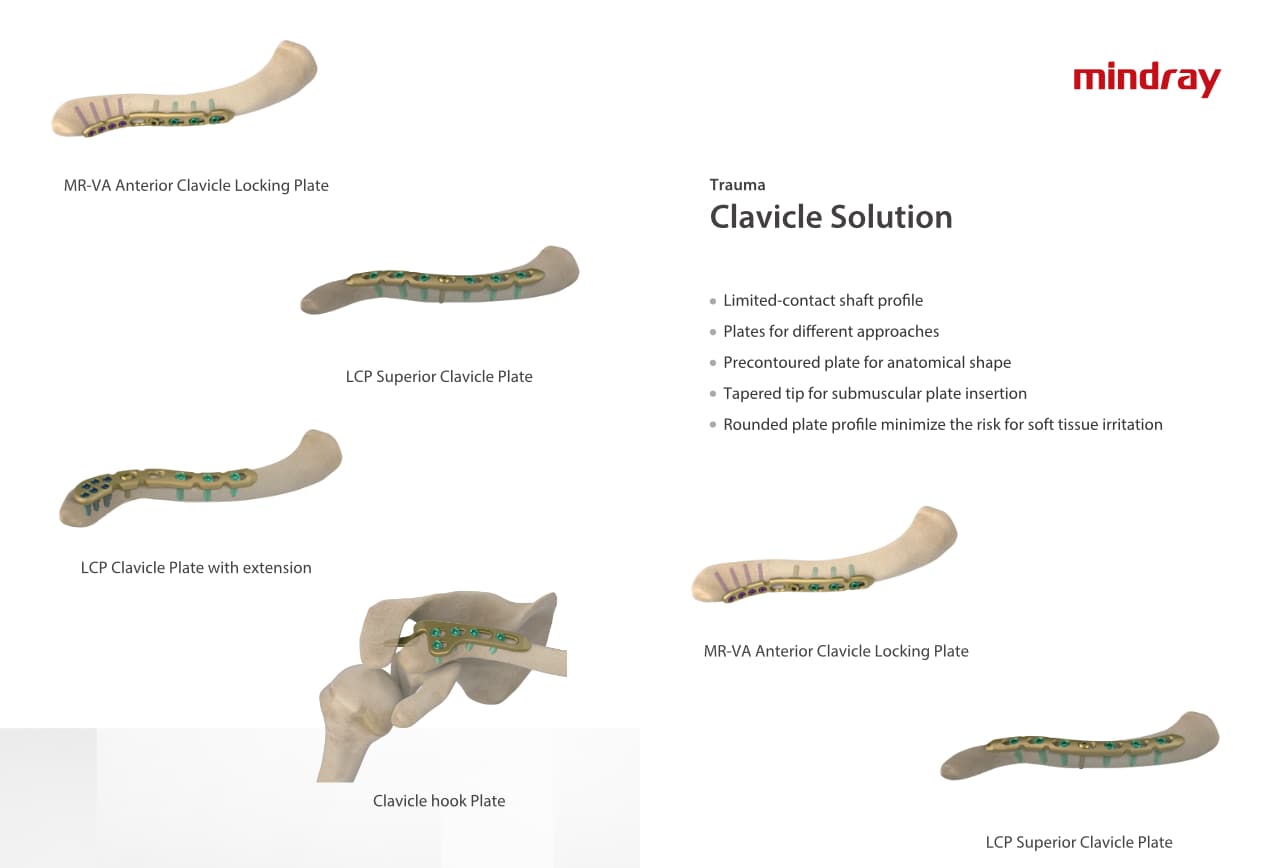

Trauma